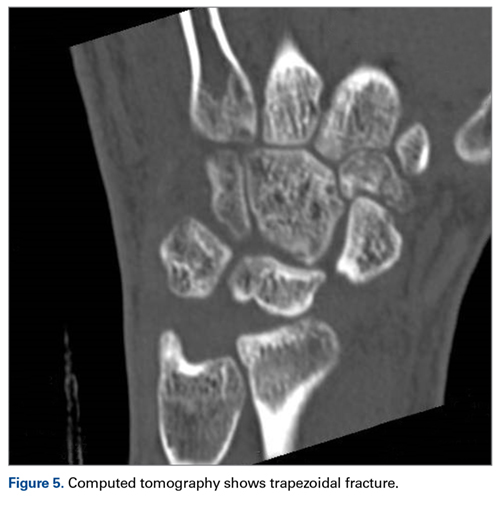

Later, however, the hand surgery team evaluated the radiograph as well as computed tomography (CT) scans and found a translunate, transradial, transtriquetral, transtrapezoid perilunate dislocation of the wrist with multiple metacarpal neck fractures ( Figures 1-5 ).The next day, with the patient under general anesthesia, an attempt to reduce the perilunate dislocation by manipulation was unsuccessful. Open reduction and internal fixation (ORIF) were performed through a dorsal approach; the perilunate dislocation was reduced and stabilized with lunocapitate 1.2-mm Kirschner wire (K-wire). The scapholunate and lunotriquetral ligaments were found to be intact, and the significantly displaced triquetral fracture was treated with internal fixation involving 2 minifragment screws ( Figure 6 ).

Our patient’s associated multiple metacarpal neck fractures can be explained by the peculiar double-impact injury with initial axial loading across the hyperextended metacarpophalangeal joint, followed by axial loading across the hyperextended and ulnar-deviated wrist, causing greater arc perilunate fracture-dislocation. The mechanism of lunate injury in this case seems to be longitudinal impaction of the capitate shearing against the volar lunate in the axial plane causing a volar lip fracture (Teisen type I), and this may be accentuated by tension in the volar radiolunate ligament. 6,7 Associated triquetral fracture in perilunate dislocation is well described in the literature. 6 However, the trapezoid fracture in our case implies a very atypical pattern of force transmission with the arc probably passing more distally through the trapezoid laterally and the triquetrum medially.